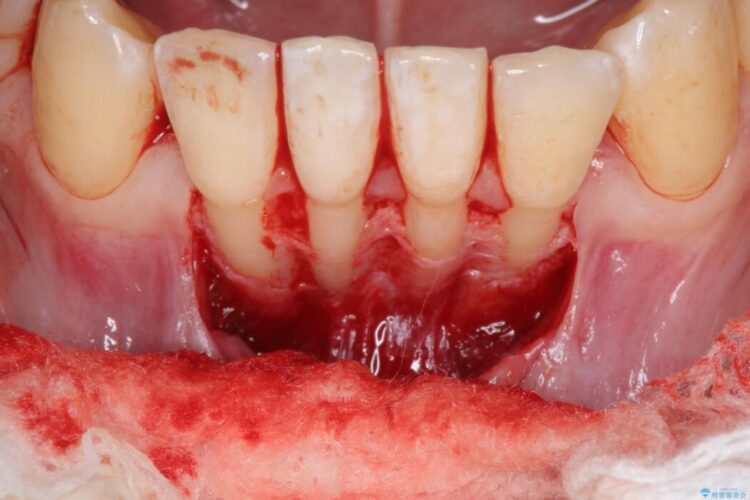

歯の根っこが露出している状態を改善するために、口蓋から結合組織を移植する方法をご提案しました。

移植した歯肉によって、露出していた歯の根っこを十分に覆うことができました。